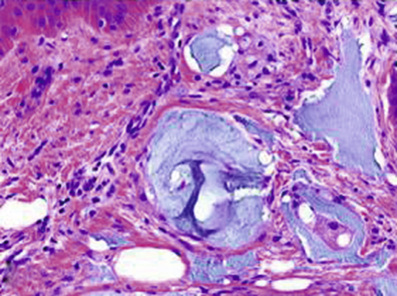

○ Linear (Fig. 7-8)

♦ IgG and C3: bullous pemphigoid, lichen planus pemphigoides, EBA, cicatricial pemphigoid, anti-p200, anti-p105, and bullous SLE

♦ IgG, IgM, IgA, and/or C3 along BMZ = lupus band (Fig. 7-9)